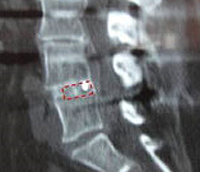

Implante endoscópico en L4/L5 para expandir pinzamientos discales sin

necesidad de recurrir a la cirugía abierta. - Vídeos